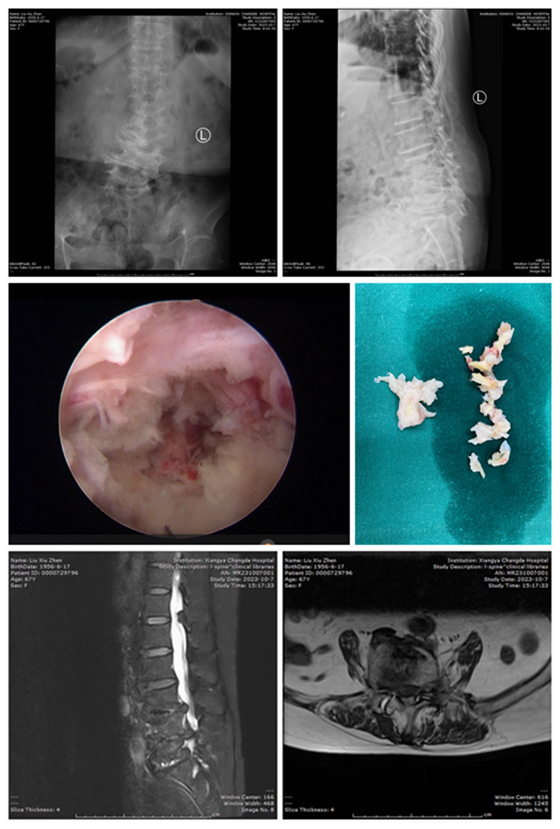

入院后,我院脊柱外科团队经详细检查,发现患者存在脊柱侧弯畸形、椎管狭窄及多节段椎间盘突出等情况。按照以往治疗经验,的确需要做钉棒手术进行矫形,但患者强烈要求尝试微创治疗。面对患者的患病实际情况和治疗诉求,脊柱外科团队再次组织讨论:刘奶奶腰痛症状并不明显,局部的侧弯已趋于稳定,而且目前刘奶奶腿部麻木疼痛及功能障碍原因是因为L4/5阶段的椎间盘脱出压迫L5神经根导致,能否行椎间孔镜微创手术治疗呢?像刘奶奶这类患者,由于长期侧弯导致局部结构较正常人出现了很大的变化,微创手术对于术者的手术水平要求很高,一旦不慎,就有神经损伤的风险。

在完善术前准备后,脊柱外科团队在硬膜外麻醉下为患者行椎间孔镜椎间盘摘除、椎管减压术,手术顺利。术后,刘奶奶立刻感到腿不痛了,第二天即可佩带腰围在女儿的搀扶下走路。但因为刘奶奶耽误时间太久,L5神经运动功能损伤,还需要一段时间的休养才能够恢复神经功能。术后第五天,刘奶奶顺利出院。

椎间孔镜下椎间盘髓核摘除术是目前治疗腰椎间盘突出最微创的术式,相对于传统腰椎开放手术,该技术具有安全性高、定位精准、术后无痛、创伤小、恢复快等优点,手术的满意度非常高。但对于部分特殊病例,穿刺置管的难度高,损伤神经的风险大,而合并脊柱侧弯畸形则更要求医生具有丰富的临床经验,进行术前精准诊断、合理规划、术中熟练操作。